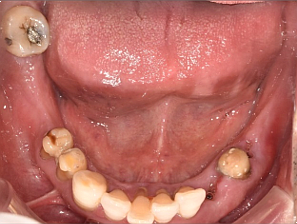

68세 남성

(전) 2021-11-05, (후) 2022-08-26

임플란트/크라운 시술 후

음식 섭취뿐만 아니라, 심미적인 개선으로

삶의 질이 높아진 환자분의 사례

치과에서 어떤 치료와 관리를 받는지에 따라 남은 삶의 질이 크게 달라질 수 있음을 절실히 느끼며